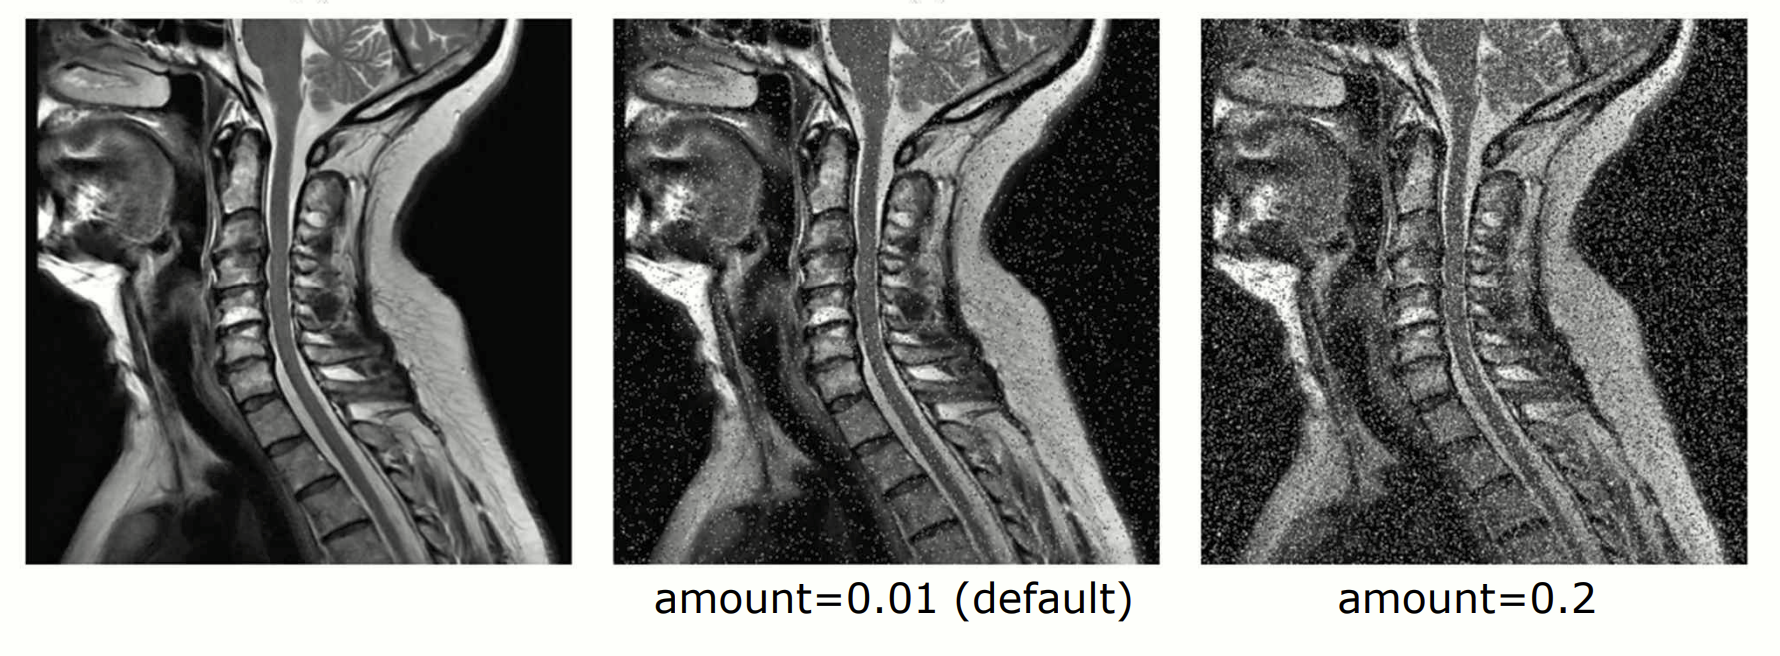

import skimage.util as su

from PIL import Image

import numpy as np

img = np.array(Image.open('neck.png'))

# s&p default s:1, p:0, amount=0.01

imgsp = su.random_noise(img, mode='s&p')

imgsp1 = su.random_noise(img, mode='s&p', amount=0.2)

skimage.util 을 이용하여 salt-and-pepper noise 를 구현할 수 있습니다. 세번째 parameter 인 amount 는 0과 1 사이의 범위로 손상시킬 정도를 지정할 수 있습니다.